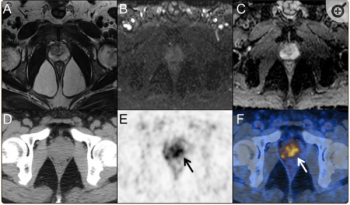

For patients 80 years of age or older that have a PSA level at 20 ng/mL or higher, PSMA PET/CT has a high likelihood of success in diagnosing and staging prostate cancer regardless of pre-imaging biopsy use, according to newly published research.